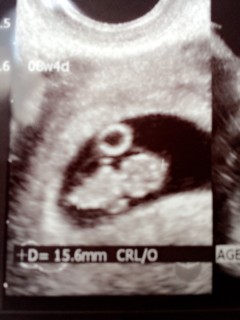

8w2Dで8W4Dの大きさ! クリオネみたいで可愛いな♪♪ 旦那に見せたら「足ないやん!」とのこと(;^ω^) 可愛いからいいの!早く会いたいな

CRL16.6mm